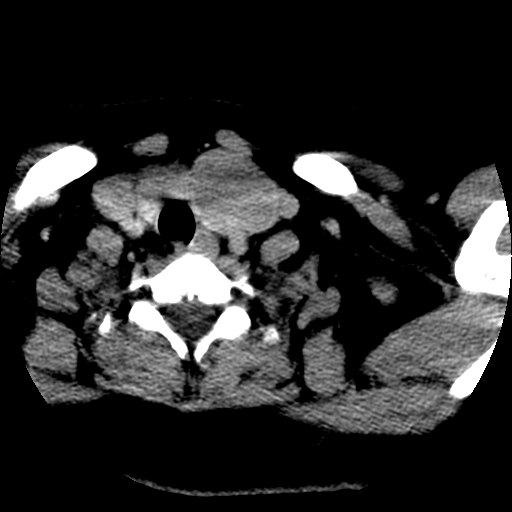

边界清,无明显强化,考虑考虑甲状腺腺瘤

腺瘤囊变

考虑左侧甲状腺腺瘤囊变。